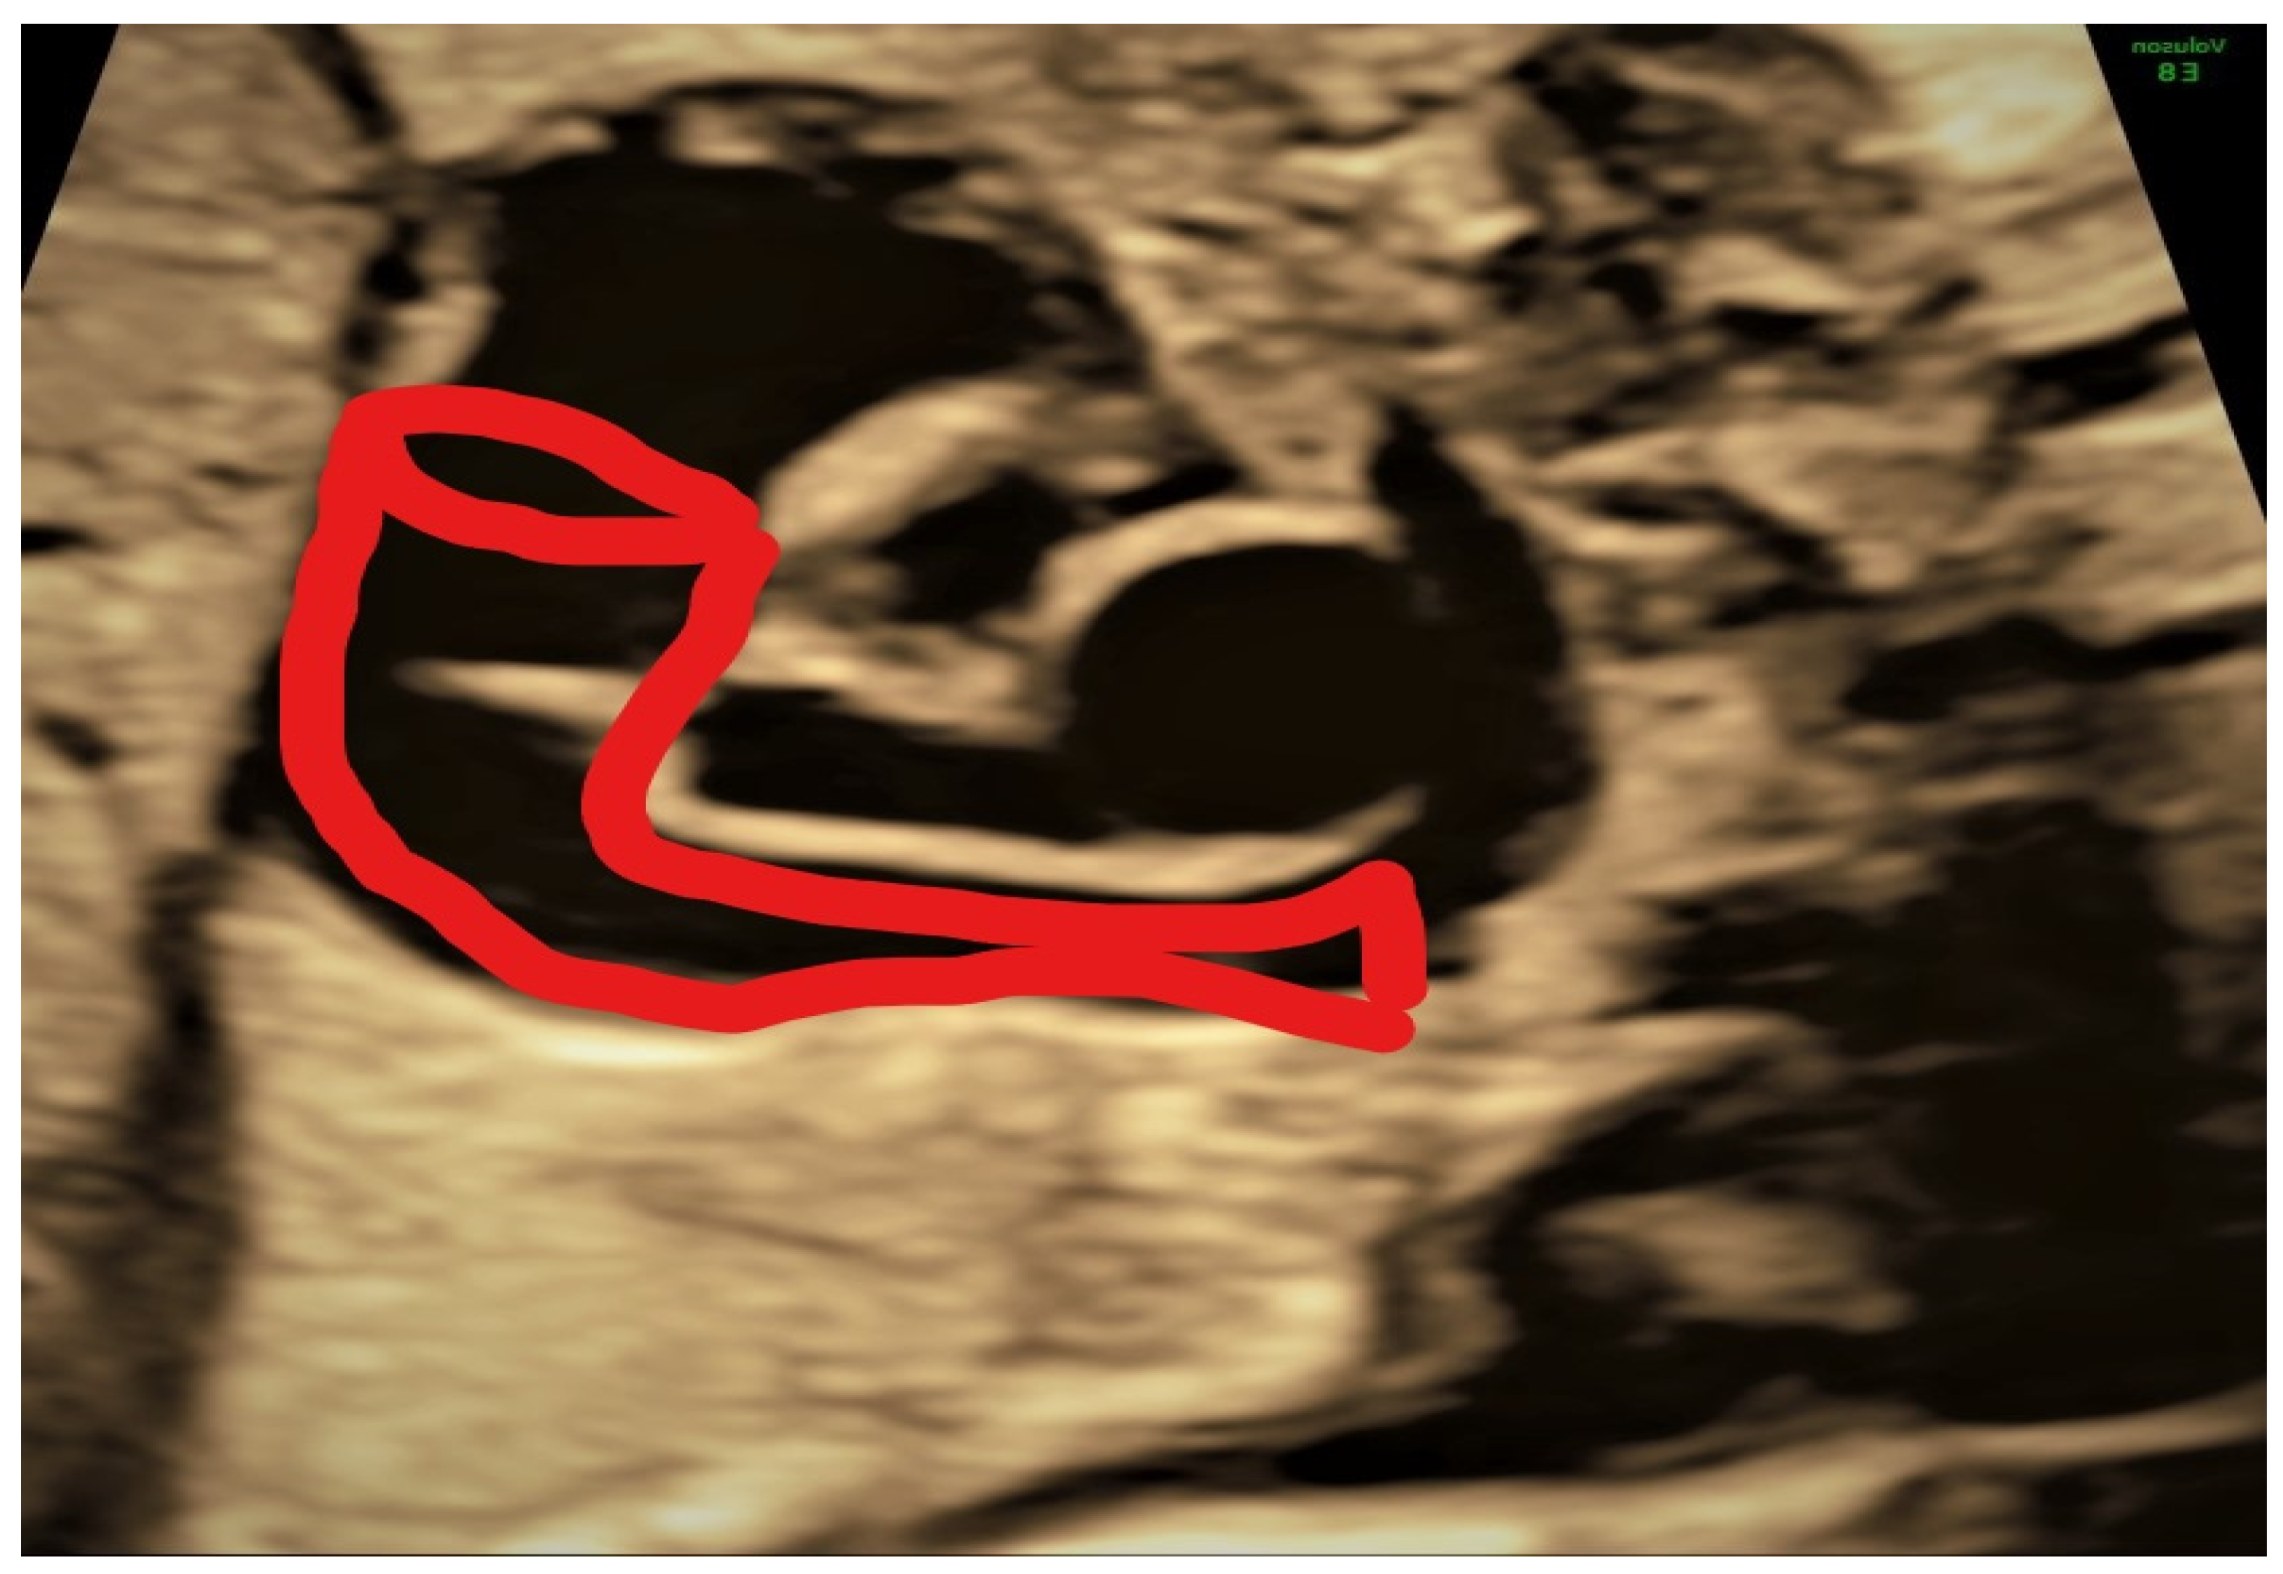

4.3. Case 3